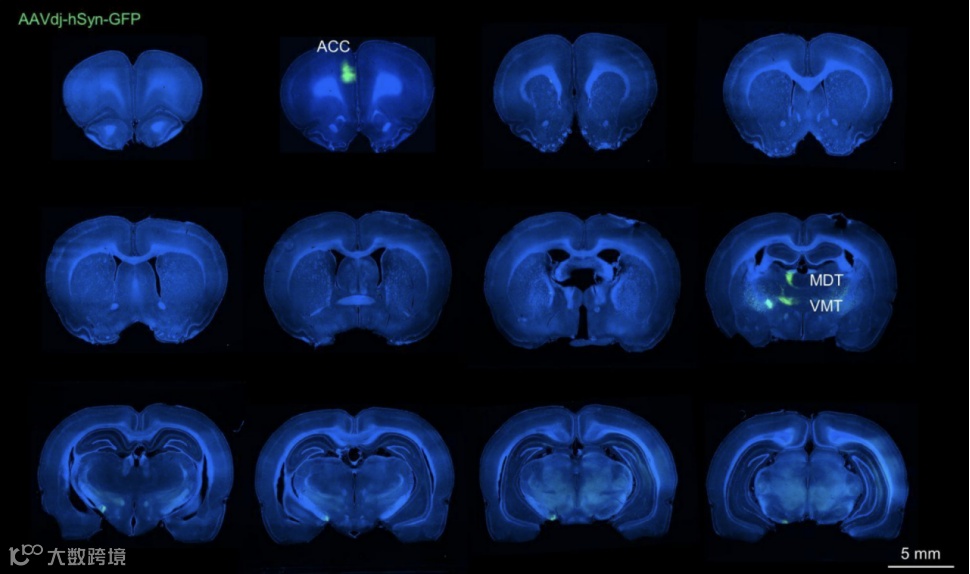

当个人收到实时反馈时,心率(HR)可以自动调节。在大鼠HR生物反馈模型中,分别刺激新皮层和内侧前脑束作为反馈和奖励。大鼠在30分钟内降低了他们的心率,在5天的3小时反馈后,心率降低了大约50%。训练后,HR的降低持续了至少10天,同时大鼠表现出焦虑行为和红细胞计数的升高。这种心动过缓是通过抑制前扣带皮质(ACC)神经元投射到丘脑腹内侧核(VMT)来预防的。ACC-VMH通路的θ节律刺激复制了心动过缓。VMT神经元投射到下丘脑背内侧(DMH), DMH神经元投射到支配心脏副交感神经的疑核。

3. 阻断从ACC投射到腹内侧丘脑核(VMT)的神经传递,可以减弱心率反馈训练诱导的心率过慢。而对VMT神经元进行光激活,则可以复制出类似的心率降低效果。这表明ACC-VMT通路在调控自主神经活动和心率方面起关键作用。

4. 进一步研究发现,VMT神经元投射到下丘脑背内侧核(DMH),DMH神经元又投射到副交感神经中枢核颈束(NAmb)。对VMT进行theta节奏刺激可以诱导心率过慢,这一效应受到阻断ACC-VMT投射的抑制。这表明ACC-VMT-DMH-NAmb构成了调控心率的关键神经通路。

图1.大脑和心脏的隐秘神经连接